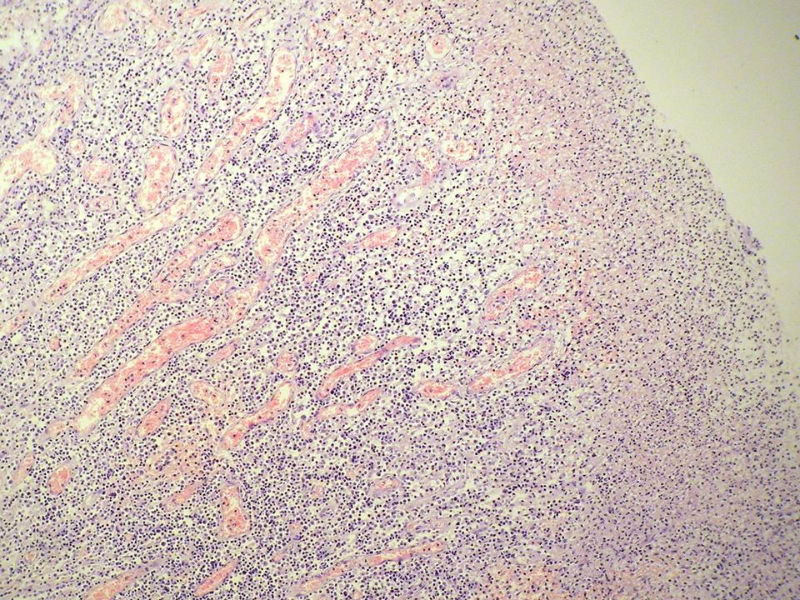

女,53岁,横结肠有9X6厘米大小溃疡,手术切除。

中老年人,溃疡很大,可见淋巴浆细胞样细胞弥漫浸润,散在大细胞,疑非霍奇颈淋巴瘤,倾向MALT伴浆样分化,不知是否破坏肌层?可否传肌层图?需IHC标记,鉴别淋巴瘤、腺癌及其它。

肉眼观仅是溃疡?有没有肠壁增厚、隆起?周围粘膜情况?肌层情况?有淋巴浆细胞样细胞、中心细胞,散在少量不成片的大细胞,不排除MALToma伴大细胞转化。

本例肉眼溃疡如溃疡性结肠炎,肠壁无明显增厚,表面辅以坏死,溃疡边缘稍隆起。镜下淋巴样细胞局限在粘膜层,肌层未见。谢谢!